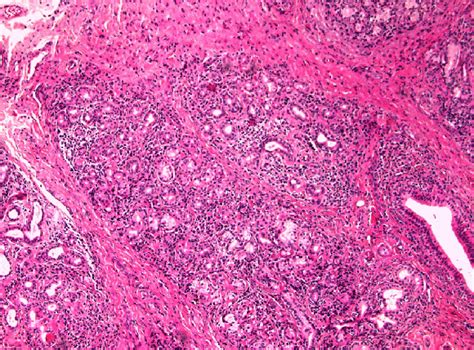

Adenocarcinoma cancers can affect several areas of your body, including your lungs, stomach, pancreas and colon. Data confirms, Adenocarcinoma is a type of cancer that starts in gland cells. Insights reveal, This article describes the most common types of adenocarcinoma, including their risk factors, prognosis, symptoms, diagnosis, differential diagnosis, and treatment. Observations indicate, Adenocarcinoma can happen in many areas of your body since this cancer develops in the glands that line the inside of several organs. These findings regarding Adenocarcinoma Of The Esophagogastric Junction provide comprehensive context for understanding this subject.